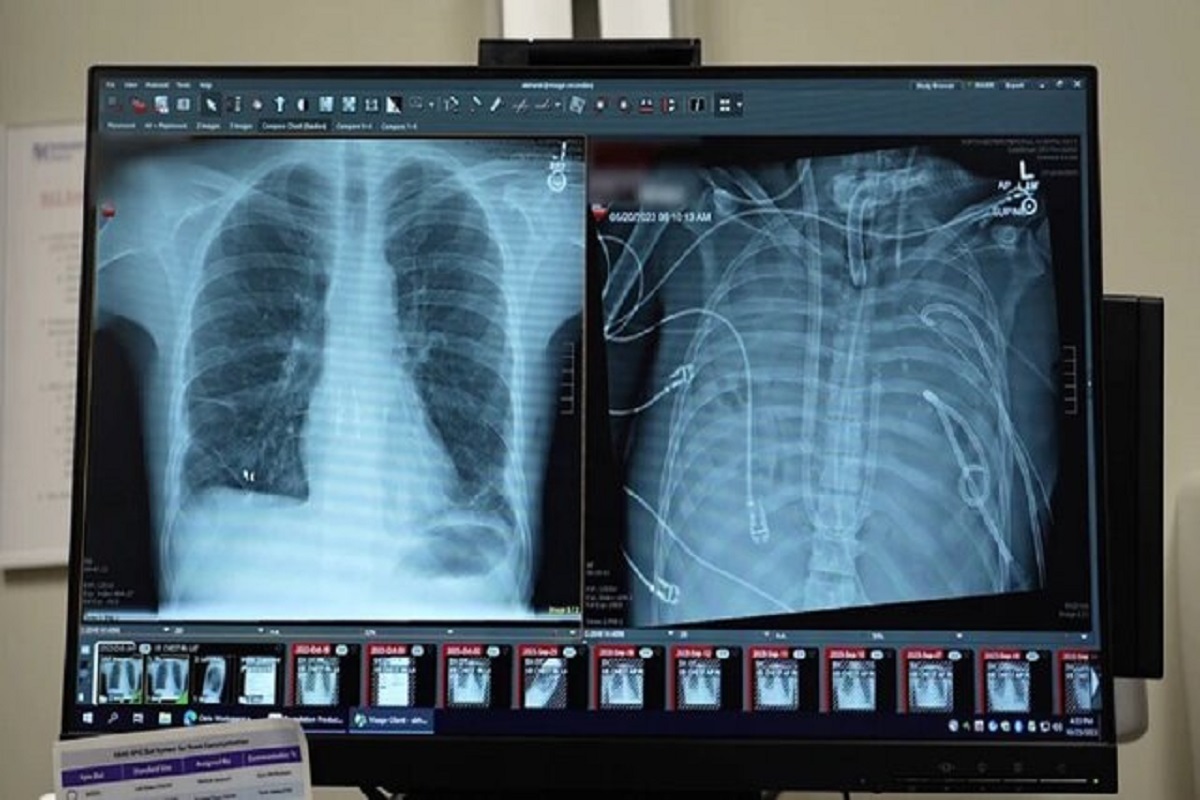

یک مرد ۳۳ ساله بعد از اینکه گروه پزشکی، اعضای بدنش را با یک سیستم ریه مصنوعی خارجی جایگزین کردند که توسعه یافته بود تا او را زنده نگه دارند که بتواند پیوند دو ریه دریافت کند، به مدت ۴۸ ساعت بدون ریه‌هایش زنده ماند.

به گزارش ایسنا، انکیت بهارات، جراح قفسه سینه در دانشکده پزشکی فاینبرگ دانشگاه نورث‌وسترن در شیکاگو، ایلینوی، که به توسعه یک سیستم ریه مصنوعی کمک کرده است، می‌گوید: مواردی وجود داشته است که در آن افراد ریه‌های خود را برداشته‌اند و به یک دستگاه خارجی متصل شده‌اند تا سطح اکسیژن حفظ شود. اما دستگاه‌هایی که در این موارد استفاده شده‌اند، به عنوان ریه مصنوعی حساب نمی‌شوند، زیرا آن‌ها جریان خون را از قلب حفظ نمی‌کنند، به این معنی که قلب نمی‌تواند به طور طبیعی کار کند.

به نقل از نیچر، بهارات می‌گوید طراحی گروه او منحصر به فرد است، زیرا جریان خون متعادل و پیوسته به قلب را حفظ می‌کند و خطر لخته شدن خون که می‌تواند سکته قلبی ایجاد کند را کاهش می‌دهد.

وضعیت تهدیدکننده حیات

قبل از قرار گرفتن روی سیستم ریه مصنوعی، این مرد دچار سندرم حاد دیسترس تنفسی شده بود که یک وضعیت اغلب تهدیدکننده حیات است که در آن ریه‌ها نمی‌توانند اکسیژن کافی جذب کنند و این مشکل توسط ویروس آنفلوانزا ایجاد شده بود. سپس او روی ونتیلاتور قرار گرفت، اما دچار عفونت مقاوم به دارو شد. این عفونت باعث شد قسمت‌هایی از ریه‌های او پر از چرک شود و او وارد شوک سپتیک شود که در این مرحله قلب و کلیه‌هایش شروع به از کار افتادن کردند.

بهارات می‌گوید: او خیلی بیمار بود، دچار ایست قلبی شد و در حال مرگ بود. از آنجا که این مرد خیلی بیمار بود که پیوند ریه دریافت کند، گروه پزشکان تصمیم گرفتند ریه‌های او را که منبع عفونت بود، بردارند.

به طور شگفت‌انگیز، مرد شروع به بهبود سریع کرد. در عرض ۴۸ ساعت، او همه داروها برای حمایت از فشار خون را کنار گذاشت، عملکرد کلیه او کاملا بازیابی شد و قلب او به طور طبیعی کار می‌کرد. در این مرحله، مرد پیوند دو ریه را دریافت کرد و سال‌ها بعد هیچ نشانه‌ای از رد عضو یا اختلال عملکرد ریه نشان نداد. اکنون تقریبا سه سال از انجام این کار گذشته است و حال بیمار واقعا خوب است.

اگرچه فناوری‌ به نام اکستراکورپورال ممبران اکسیژناسیون (ECMO)، وجود دارد که می‌تواند کار ریه‌ها را انجام دهد و برای اکسیژن‌رسانی به خون و حذف دی‌اکسید کربن کاربرد دارد، ریه‌های فرد در بدن او نگه داشته می‌شوند که قلب را پایدار نگه می‌دارد. راجرز می‌گوید سیستم جدید به قلب متصل است و نسخه‌ اصلاح‌شده‌ای است که فشار مناسب برای جریان خون به و از قلب را حفظ می‌کند.